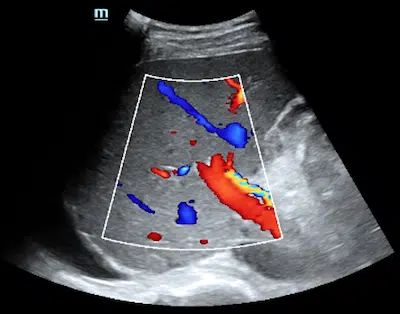

A liver ultrasound is a non-invasive diagnostic test that uses sound waves to produce images of the liver. [1]The sound waves bounce off the liver’s tissues and create a visual representation of its internal structure to detect potential problems before they become severe.

Medical professionals frequently use this imaging examination to detect ailments, including cirrhosis, fatty liver disease, and liver tumors. Furthermore, it can effectively uncover any irregularities within the bile ducts and blood vessels that serve the liver.

• A 2D liver ultrasound is a non-invasive test that produces standard, two-dimensional, grayscale images of a person’s liver and blood vessels. 2D ultrasounds can help to screen for various liver conditions, including fatty liver, cirrhosis, hepatitis, liver tumors, diseases of the biliary system, and blood flow abnormalities. Indications for this exam could include abdominal, flank, and/or back pain, jaundice, palpable abnormalities, such as an abdominal mass or organomegaly, and abnormal laboratory values.